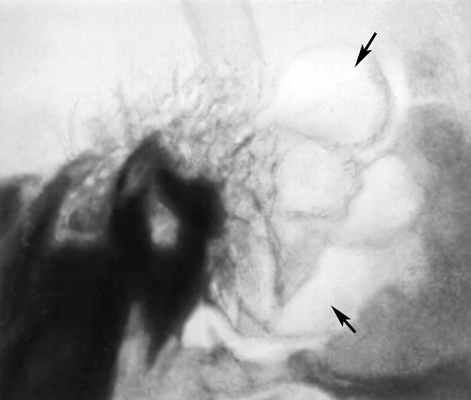

очаг разрежения костной ткани (указан стрелками)">

Рис. б). Рентгенограмма левой височной кости (боковая проекция) при гнойном мастоидите — на месте ячеистой структуры сосцевидного отростка виден очаг разрежения костной ткани (указан стрелками).